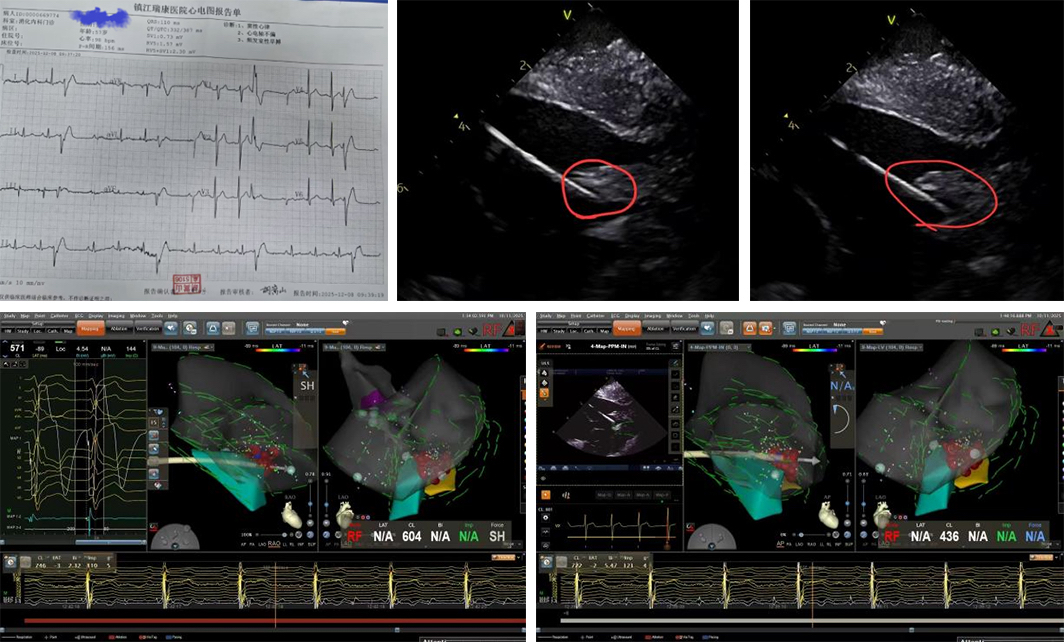

扬子晚报网12月25日讯(通讯员 刘柳 记者 万凌云 姜天圣)近日,镇江瑞康医院心内科在首席专家严金川教授精心组织下,成功完成两例心腔内超声(ICE)指导下左室乳头肌室早消融术,该技术是应用ICE精准指导结合三维标测系统,准确定位治疗乳头肌起源的室性早搏。

乳头肌起源的室性早搏因解剖结构特殊(如活动度大、导管贴靠困难),传统消融成功率较低。ICE技术通过将超声导管置入心脏,实时构建心腔三维图像,精准定位乳头肌并指导消融导管到位,提高成功率和安全性。

两例患者均为频发室性早搏,24动态心电图室早总数15000次左右,经多种药物治疗效果不佳,严重影响生活质量,遂慕名至镇江瑞康医院心内科就诊。结合患者体表心电图及腔内电生理标测结果,最终确定室早来源于左室后乳头肌内,消融术后动态心电图为极少数室性早搏,手术圆满成功。